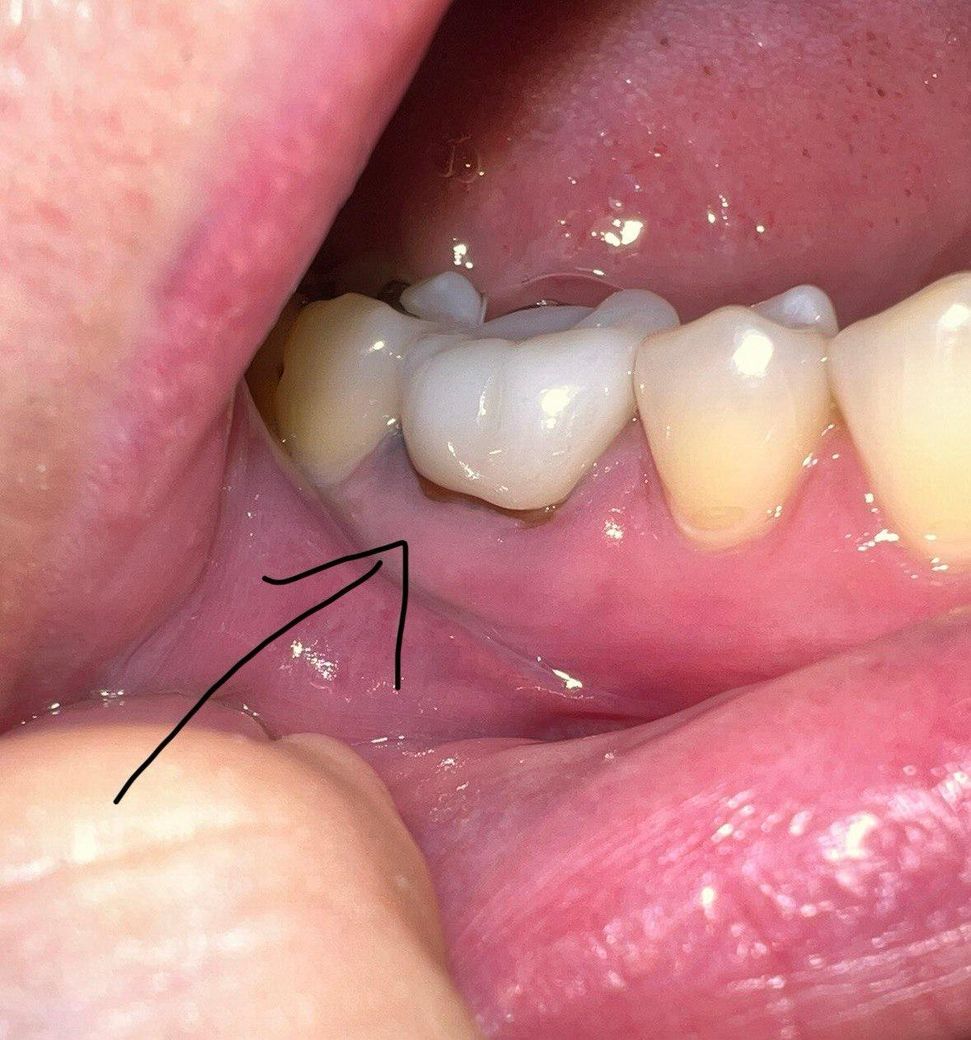

약 5년전 어금니에 크라운을 씌웠는데

오늘 우연히 거울을 보니 아래 사진처럼 잇몸이 살짝 녹아서(?) 내부 치아가 드러나있는걸 발견했습니다.

다행히 시리거나, 통증이 있거나, 크라운이 흔들리거나, 피가 나는 등의 문제는 없습니다.

보철치료를 하고 난다음 경계부위가 내려가면서 보철물의 경계가 보일수 있습니다. 크게 문제가 되지는 않지만 심미적으로 신경이 쓰인다면 보철치료를 다시 받는 것이 좋을수 있습니다.

나이가 들면서 잇몸이 퇴축되면서 치아의 뿌리가 약간 노출된거 같습니다. 일단은 관리를 하시면서 사용하셔도 될것같습니다.

간혹 시간이 지남에 따라 저렇게 잇몸이 내려가긴 하지만 주위 잇몸 상태가 건강한 것으로 보아 병적인 상태는 아니니 걱정하지 않으셔도 되겠습니다.